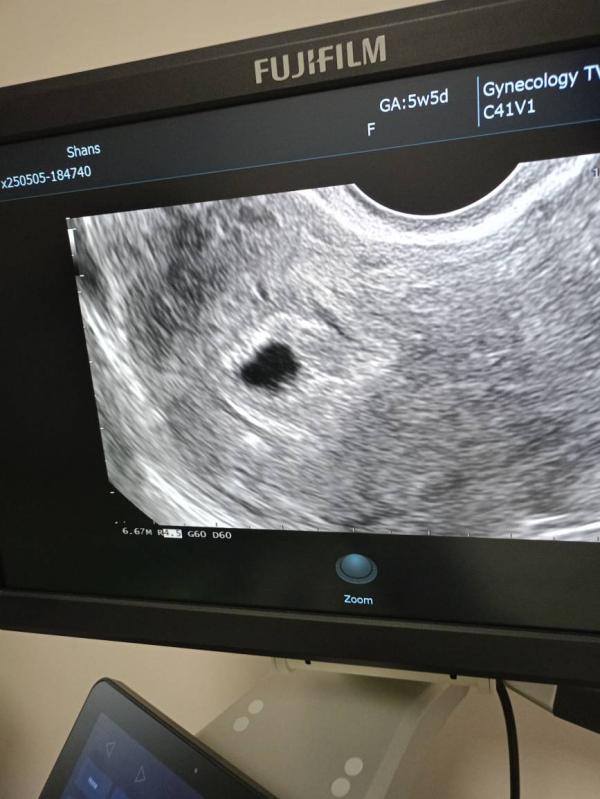

Первое УЗИ от 5 мая 2025г

Маточная беременность срок 4-5 недель

Акушерский срок 6 недель ( разница неделя).